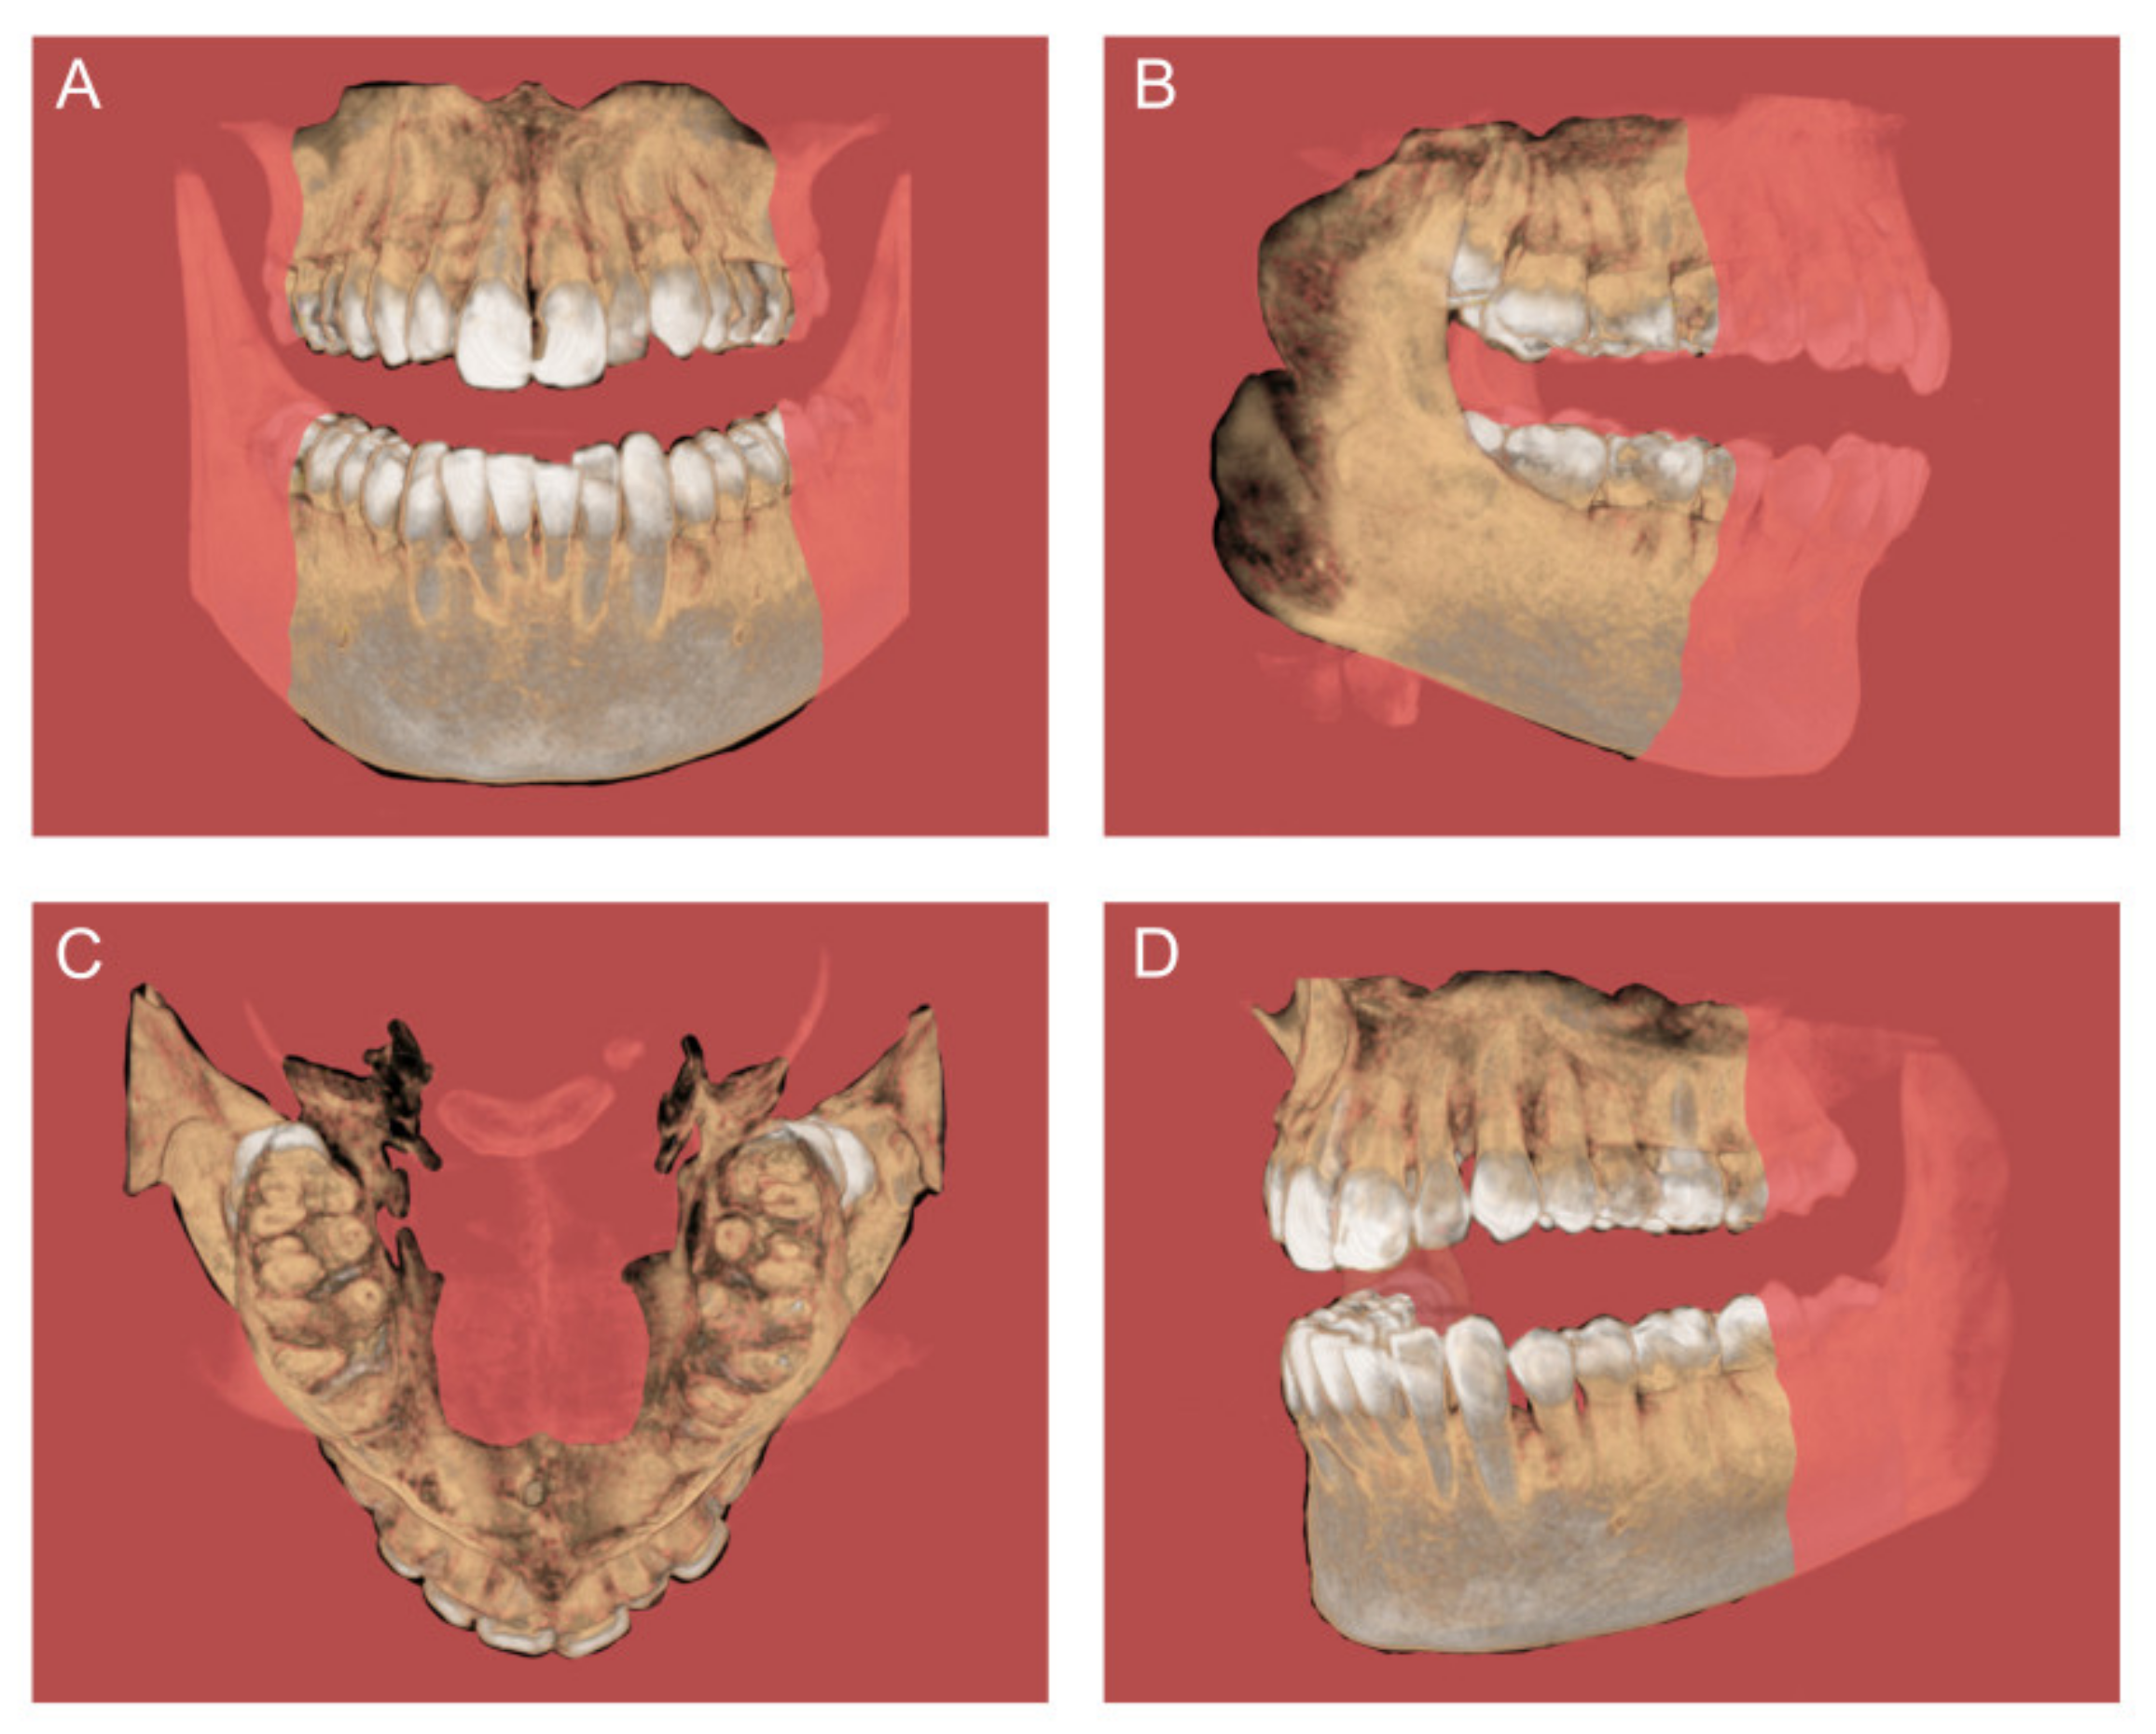

- Pavlovic, Z.R.; Milanovic, P.; Vasiljevic, M.; Jovicic, N.; Arnaut, A.; Colic, D.; Petrovic, M.; Stevanovic, M.; Selakovic, D.; Rosic, G. Assessment of Maxillary Molars Interradicular Septum Morphological Characteristics as Criteria for Ideal Immediate Implant Placement—The Advantages of Cone Beam Computed Tomography Analysis. Diagnostics 2022, 12, 1010. [Google Scholar] [CrossRef] [PubMed]

- Milenkovic, J.; Vasiljevic, M.; Jovicic, N.; Milovanovic, D.; Selakovic, D.; Rosic, G. Criteria for the Classification of the Interradicular Septum Shape in Maxillary Molars with Clinical Importance for Prosthetic-Driven Immediate Implant Placement. Diagnostics 2022, 12, 1432. [Google Scholar] [CrossRef] [PubMed]